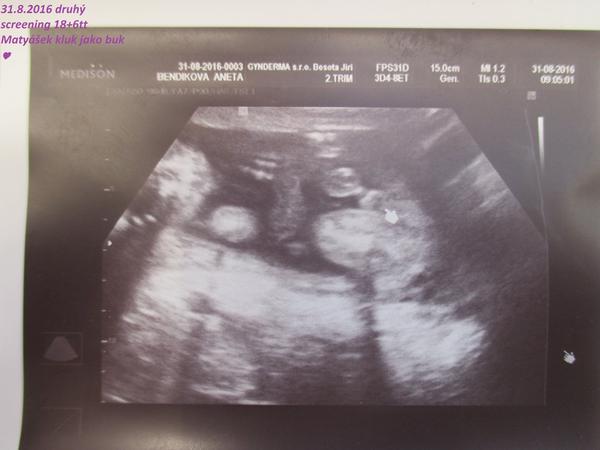

@mudchen jé tak to moc gratuluji 🙂 co bych za to dala kdyby mi 31.8 na druhém screeningu řekli,že je to taky holčička,ale určitě nebudu mít takové štěstí jako ty... ale co už toho broučka v bříšku miluji 🙂

@mudchen moc děkuji 🙂 🙂 ale nevěřím tomu,že by šulínek upadl 😀 😀 ale určitě tu dám vědět jak jsem dopadla 🙂 🙂

@rennye no podle mě to na chlapíka vypadá 😀 mám podobnou fotečku s dneška 😀

takže mám v bříšku třetího chlapečka 😀

@juliemichal A ty už máš chlapečka potvrzeného? Tak to budeme pravděpodobně na stejné vlně, 3 kluci :-*. Na té tvé fotce to je označen pytlík i pindík?

@rennye ano ano už ho mám na 100% potvrzeného s dnešního screeningu 😀 na té mé fotce je jen označen pytlík 😀 pindíka měl schovaný za pupeční šňůrou 😀